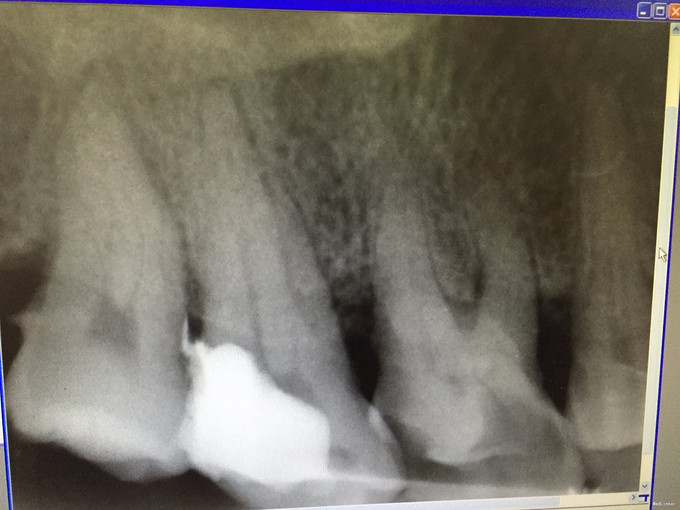

检查: #17#18之间出现大量食物残渣,去除后见大量腐质及牙色充填体,去腐后见穿髓孔,#17叩(+-),松(-),冷热测不适,电测有活力,扪诊无不适,#18叩(-),松(-),冷热侧正常,电测有活力,牙龈稍红肿。 X线示: #17高密度充填体,根尖未见明显阴影。

诊断:#17慢性牙髓炎 处理: #17碧兰麻下开髓、揭全顶,寻找根管口,拔髓,次氯酸钠和双氧水交替超声冲洗,测量工作长度,根管预备,封Ca(OH)糊剂2两周,ZOE暂封。两周后复诊检查,患牙无叩痛,患者无不适,暂封存。去暂封,次氯酸钠和双氧水交替超声冲洗,再次测量工作长度,干燥,热牙胶充填。树脂充填治疗。